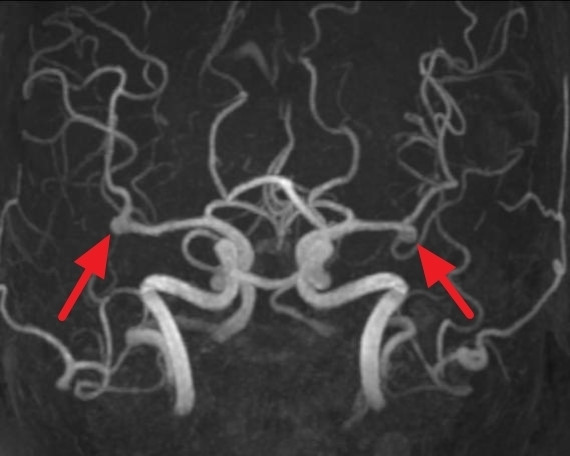

뇌동맥류의 진단

뇌동맥류는 다음과 같은 검사를 통해 진단합니다.

- 자기공명영상(MRI): 뇌의 상세한 영상을 제공하여 동맥류의 위치와 크기를 파악하는 데 도움이 됩니다.

- 뇌혈관 조영술: 혈관 내에 조영제를 주입하여 X선 촬영을 통해 동맥류의 정확한 모양과 위치를 확인합니다.